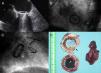

Transesophageal echocardiogram (A) and fluoroscopy (B and C) showing impaired motion of the two leaflets due to associated pannus and thrombosis; (D) explanted mechanical mitral valve. The shape of pannus growth on the ventricular surface of the prosthesis removed from the prosthesis can be clearly seen. The concentric stenosis of the valve orifice area (black arrow) and the thrombosis on the atrial side causing valve blockage (white arrow) are evident. The mural blood clot removed from the left atrial appendage is shown.

Through median resternotomy, adherences from the previous surgery were carefully released. Cardiopulmonary bypass was established with bicaval venous cannulation. Through transseptal access, the mitral prosthesis was accessed and examined. Intraoperatively, a 3×3 cm thrombus was removed from the origin of the left atrial appendage (not closed during the first cardiac operation) and in immediate contact with the mechanical valve (Figure 1D). A partial thrombosis was observed around the mechanical valve and an immobile prosthesis disc was seen. The mitral prosthesis was replaced and the mechanical valve was excised, revealing circumferential mitral prosthesis obstruction due to pannus growing within the valve orifice on the ventricular surface of the prosthesis. The valve was replaced with a 31-mm Labcor mitral bioprosthesis and tricuspid annuloplasty was also performed. Echocardiographic monitoring confirmed that the mitral prosthesis was functioning correctly without leakage after placement. Postoperatively, the patient recovered uneventfully and was discharged home nine days after surgery with greater exercise tolerance and progressive improvement.

A 78-year-old woman with a history of hypertension and diabetes was admitted to our institution with a one-year history of progressive dyspnea. Ten years previously she had been diagnosed with rheumatic heart disease and atrial fibrillation and had undergone mitral valve replacement with a 25-mm Carbomedics bileaflet mechanical valve. She had been asymptomatic until two months ago, when she reported dyspnea (New York Heart Association class III), orthopnea, and weight gain. Physical examination revealed cardiac arrhythmia and signs of decompensated heart failure (ascites and lower limb edema). Laboratory tests showed no abnormalities. The electrocardiogram confirmed atrial fibrillation. An echocardiogram revealed restricted motion of the mitral leaflets (Figure 1A), with partial thrombosis of the mitral prosthesis and a blockage of the posterior mechanical prosthesis disc. A high transmitral gradient was observed by transesophageal echocardiography. A left atrial (LA) mural thrombus, moderately depressed left ventricular ejection fraction (45%), severe pulmonary artery hypertension (systolic pulmonary artery pressure of 70 mmHg), and severe functional tricuspid regurgitation were also detected. A coronary angiogram confirmed an immobile prosthetic leaflet (Figure 1B and 1C). No lesions were seen in the main coronary arteries. The patient was scheduled for cardiac surgery.